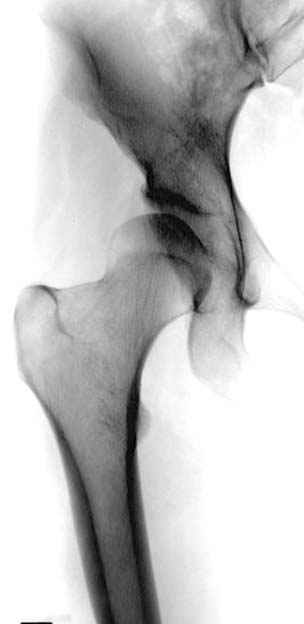

Но, занимаясь с этой патологией, собрал небольшой опыт в лечении остеоартрита, включая: периацетабулярную (ориентационно-корригирующую) остеотомию, и на проксимальной части бедра - valgus, varus, flexion and extension osteotomy и в комбинациях, базирующуюся на авангардных учениях Reinhold Ganz из Bern, на конгруентности сустава и увеличения контактной площади в суставе для уменьшения давления на площади хряща, При Вашем желании можно продемонстрировать результаты наших операций на слайдах.

Понимаю и поддерживаю Вас, что связка головки бедра и вся биомеханика сустава имеет большое значение для стабильности, и является немаловажным фактором в приобретенном остеоартрите, и я за необходимость изучения, но никах не могу понять разницу двух снимков (кстати, очень оригинальный дизайн), хотя Вы даете обоснование, что один из них без связки. Не могли бы Вы обьяснить суть эксперимента? На прямой вопрос Др. Челнокова вы отвечаете глубоким размышлением о философии движения спортивной ходьбы и маникенщиц, а представленный неточный рисунок тазобедренного сустава не отвечает сути заданного вопроса.

Моя идея, это не моя идея см. (Бытие, 32.32), правильнее было бы сказать идея, которую я озвучил, - результат не только анализа литературы. Выявление неточностей и парадоксов в работах наших авторитетов, дала только часть доказательств. Была создана трехмерная модель тазобедренного сустава с аналогом связки головки бедра. Я согласен фото, которые представлены на Ортофоруме получились низкого качества, в этот раз я вышлю более качественные… Коллега, отличие в моделях представленных на фотографиях только одно - в одной из них есть аналог связки головки бедра в другой его нет. И только это единственное отличие обеспечивает, разгрузку динамометра имитирующего отводящую группу мышц. Кто-либо из Наших авторитетов экспериментировал на подобных моделях содержащих аналог связки головки бедра…, а Вы? Сообщите, Пожалуйста, источник. Вы смотрите на фотографии и отказываетесь верить своим глазам, я Вас не понимаю. Наконец, сделайте сами подобную конструкцию, я вышлю вам эскизы. Вам потребуется: однополюсной эндопротез с отверстием в головке, запчасти из набора к аппарату Илизарова, стандартные гири для скелетного вытяжения, кусок капронового шнура, примитивный бытовой динамометр (безмен) все это Вы легко найдете. Сложнее будет сделать аналог вертлужной впадины с полулунной поверхностью, вырезкой и ямкой соответствующих по размеру головке ½ ее диаметра. Найдите токаря и фрезеровщика достаточной квалификации, и то, что является в Вашем регионе свободно-конвертируемой валютой, и Вы обретете, менее чем за один рабочий день, искомое… А суть эксперимента проста - нагрузить трехмерную модель ТБС подобно тому как нагружается реальный ТБС в одноопорном положении, сначала без аналога связки головки бедра, а затем с таковым.

«Авангардное учение Reinhold Ganz из Bern», основанное на улучшении конгруэнтности в ТБС и увеличении контактной площади в суставе для уменьшения давления на хрящ, как раз и доказывают, что ведущей причиной деструкции хряща при коксартроза являются высокие напряжения в верхнем секторе сустава. В норме напряжения здесь существенно меньше, чем в нижнем секторе. Reinhold Ganz из Bern манипулируя с суставными концами, как раз и пытается снизить возникающие при артрозе высокие среднепостоянные напряжения. За счет более толстого хряща и некоторых других компенсаторных механизмов ТБС некоторое время компенсирует всплеск среднепостоянных напряжений, но механика берет свое, хрящ истирается, а когда кость начинает тереться о кость даже большая площадь их контакта не поможет, поговорите с пациентами. Интересно отметить, что при высокой способности организма к компенсации он сам без Ваших остеотомий значительно увеличивает площадь контакта при коксартроза за счет деформаций, углублений вертлужной впадины, ликвидации ямки головки бедра, краевых разрастаний… С большим желанием ознакомлюсь с Вашими результатами операций на слайдах, но еще больше будет интересно посмотреть их результат через несколько лет, и поговорить с пациентами, а потом с тем, кто будет протезировать этот обезображенный сустав.